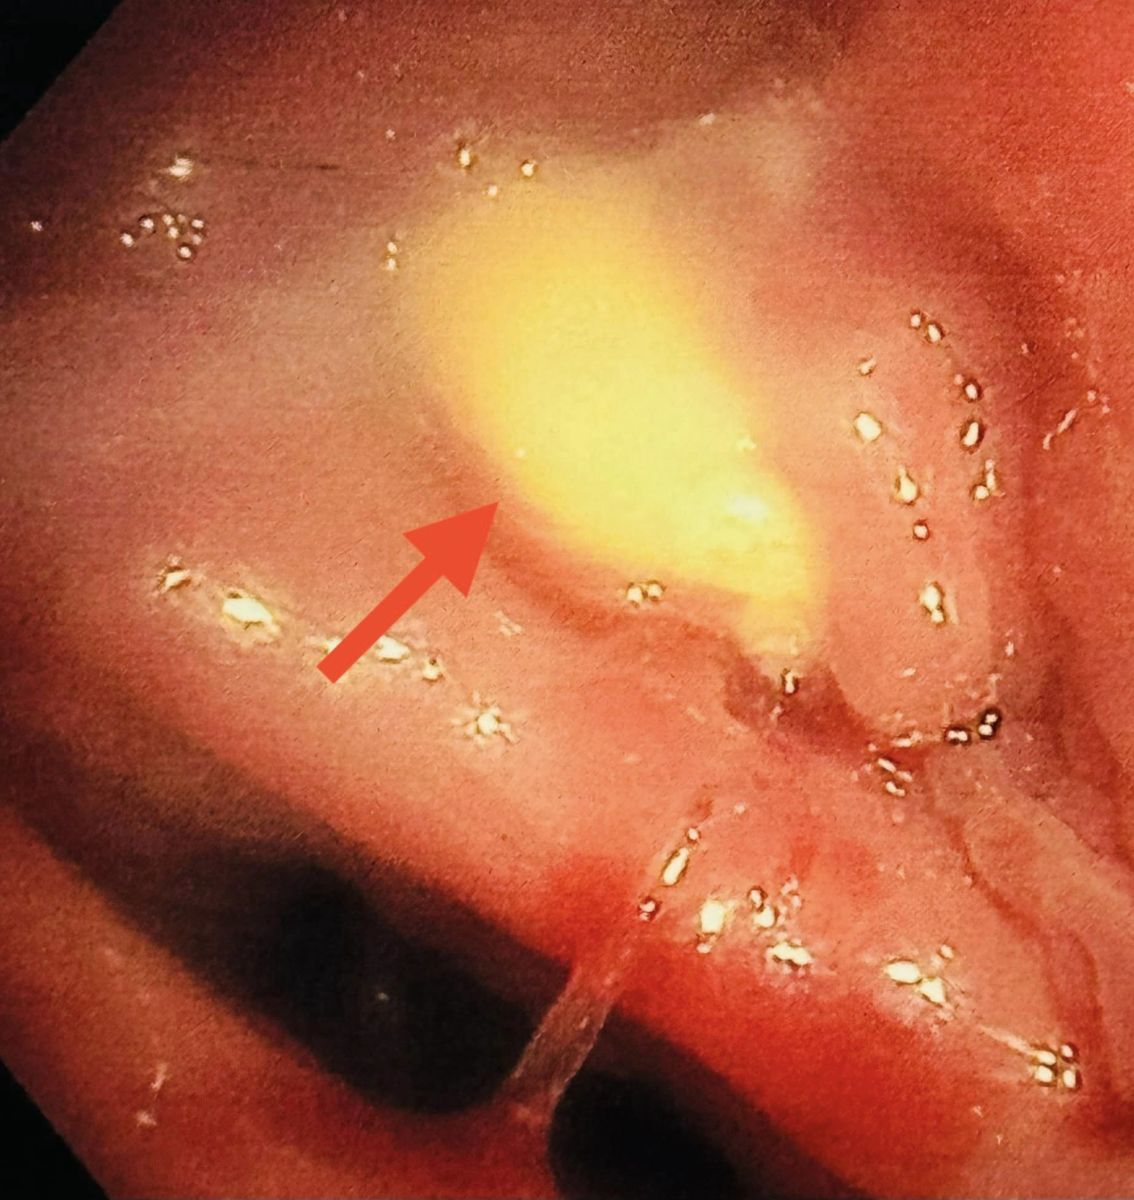

นพ.มนูญ ระบุว่า ผู้ป่วยชายอายุ 87 ปี เป็นโรคหัวใจ เบาหวาน ความดัน ไขมันในเลือดสูง โรคถุงลมโป่งพอง มีประวัติสำลักอาหารบ่อย ปลายเดือนมีนาคม 2567 เริ่มมีไข้ ไอ มีเสมหะ เอกซเรย์ปอดมีฝ้าขาวกลีบบนด้านซ้าย ให้ยาปฏิชีวนะรักษาปอดอักเสบติดเชื้อ ดีขึ้นชั่วคราว แล้วก็กลับมาเป็นซ้ำอีก จึงทำคอมพิวเตอร์ปอดวันที่ 25 เมษายน พบหลอดลมของปอดข้างซ้ายบนอุดตัน และปอดกลีบบนข้างซ้ายอักเสบและแฟบเล็กน้อย วันที่ 1 พฤษภาคม ได้ทำการส่องกล้องเข้าไปในหลอดลม เห็นสิ่งแปลกปลอมสีเหลืองผิวเรียบอุดปิดหลอดลมของปอดข้างซ้ายด้านบน ไม่สามารถคีบเอาสิ่งแปลกปลอมออกได้ ตัดชิ้นเนื้อก้อนนี้ส่งตรวจทางพยาธิวิทยา อ่านว่าเป็น “พืช”

ได้ปรึกษาศัลยแพทย์ผ่าตัดทรวงอก แนะนำทำการผ่าตัดเข้าไปในทรวงอกโดยการส่องกล้อง Video-Assisted Thoracic Surgery (VATS) เพื่อไปผ่าตัดเปิดหลอดลม bronchotomy เอาสิ่งแปลกปลอมออก

ได้ทำการผ่าตัดวันที่ 9 พฤษภาคม เมื่อผ่าตัดเปิดหลอดลมของปอดข้างซ้ายด้านบน พบสิ่งแปลกปลอมเป็นก้อนสีเหลืองพยายามคีบดึงไม่ออก ต้องบีบให้แตกเป็นชิ้นเล็กๆ แล้วจึงดึงออกมาได้ ก้อนนิ่มไม่แข็ง พบหนองในหลอดลมด้วย ให้ยาปฏิชีวนะรักษาปอดติดเชื้อตามความไวของเชื้อแบคทีเรียต่อยา ไม่พบเนื้องอกหรือมะเร็ง